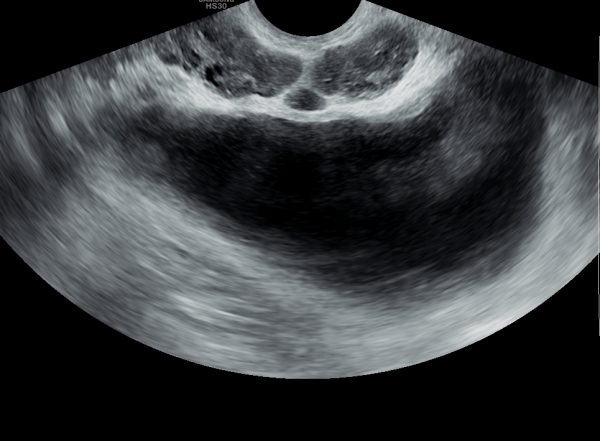

주 2~3회 전립선의 표적 치료후 사정관의 순환 장애가 개선되어 사정관의 낭종과 만성 골반통 증후군 그리고 배뇨장애 등의 증상이 개선 되었으나 사정관내 탈락된 상피 세포의 치료와 관리가 필요한

추적 경직장 전립선 초음파 사진입니다.

This is a follow-up transrectal prostate ultrasound image taken after targeted prostate therapy performed 2–3 times per week. The treatment has improved circulation in the ejaculatory ducts, leading to a reduction in ejaculatory duct cysts, chronic pelvic pain syndrome, and urinary symptoms. However, further treatment and management of the exfoliated epithelial cells within the ejaculatory ducts are still necessary.